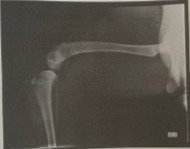

Lalinha é uma cachorrinha cuidada por um protetor onde existem vários animais. Em novembro, infelizmente, ela sofreu um atropelamento. Uma de suas patas traseiras teve fratura exposta e dilaceração da pele. Levamos ela para uma urgência veterinária, pois ela estava sangrando muito, e não parava de tremer.